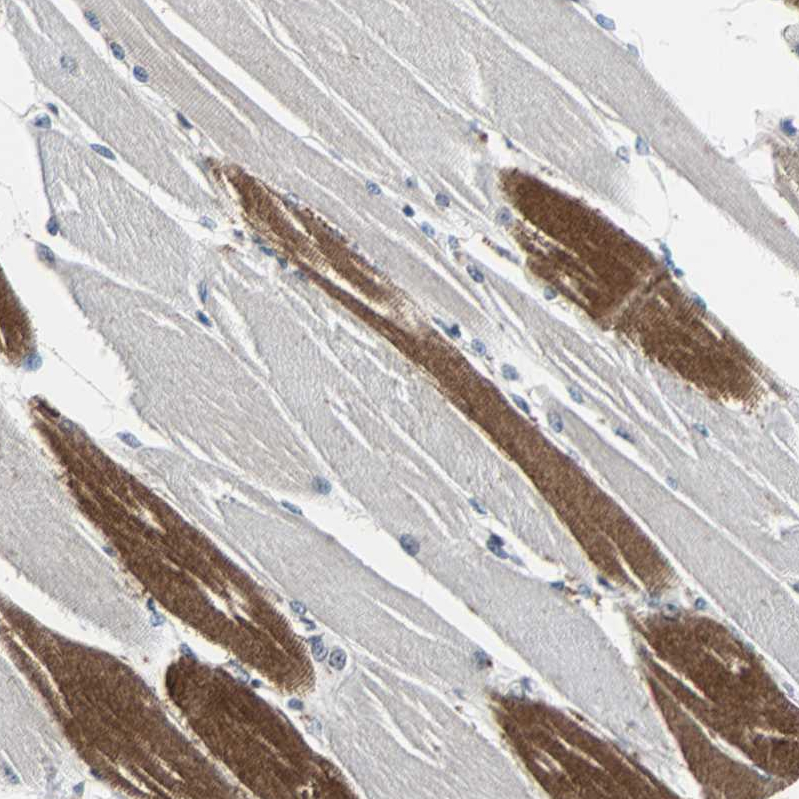

Immunohistochemical staining of human stomach shows strong membranous positivity in glandular cells.